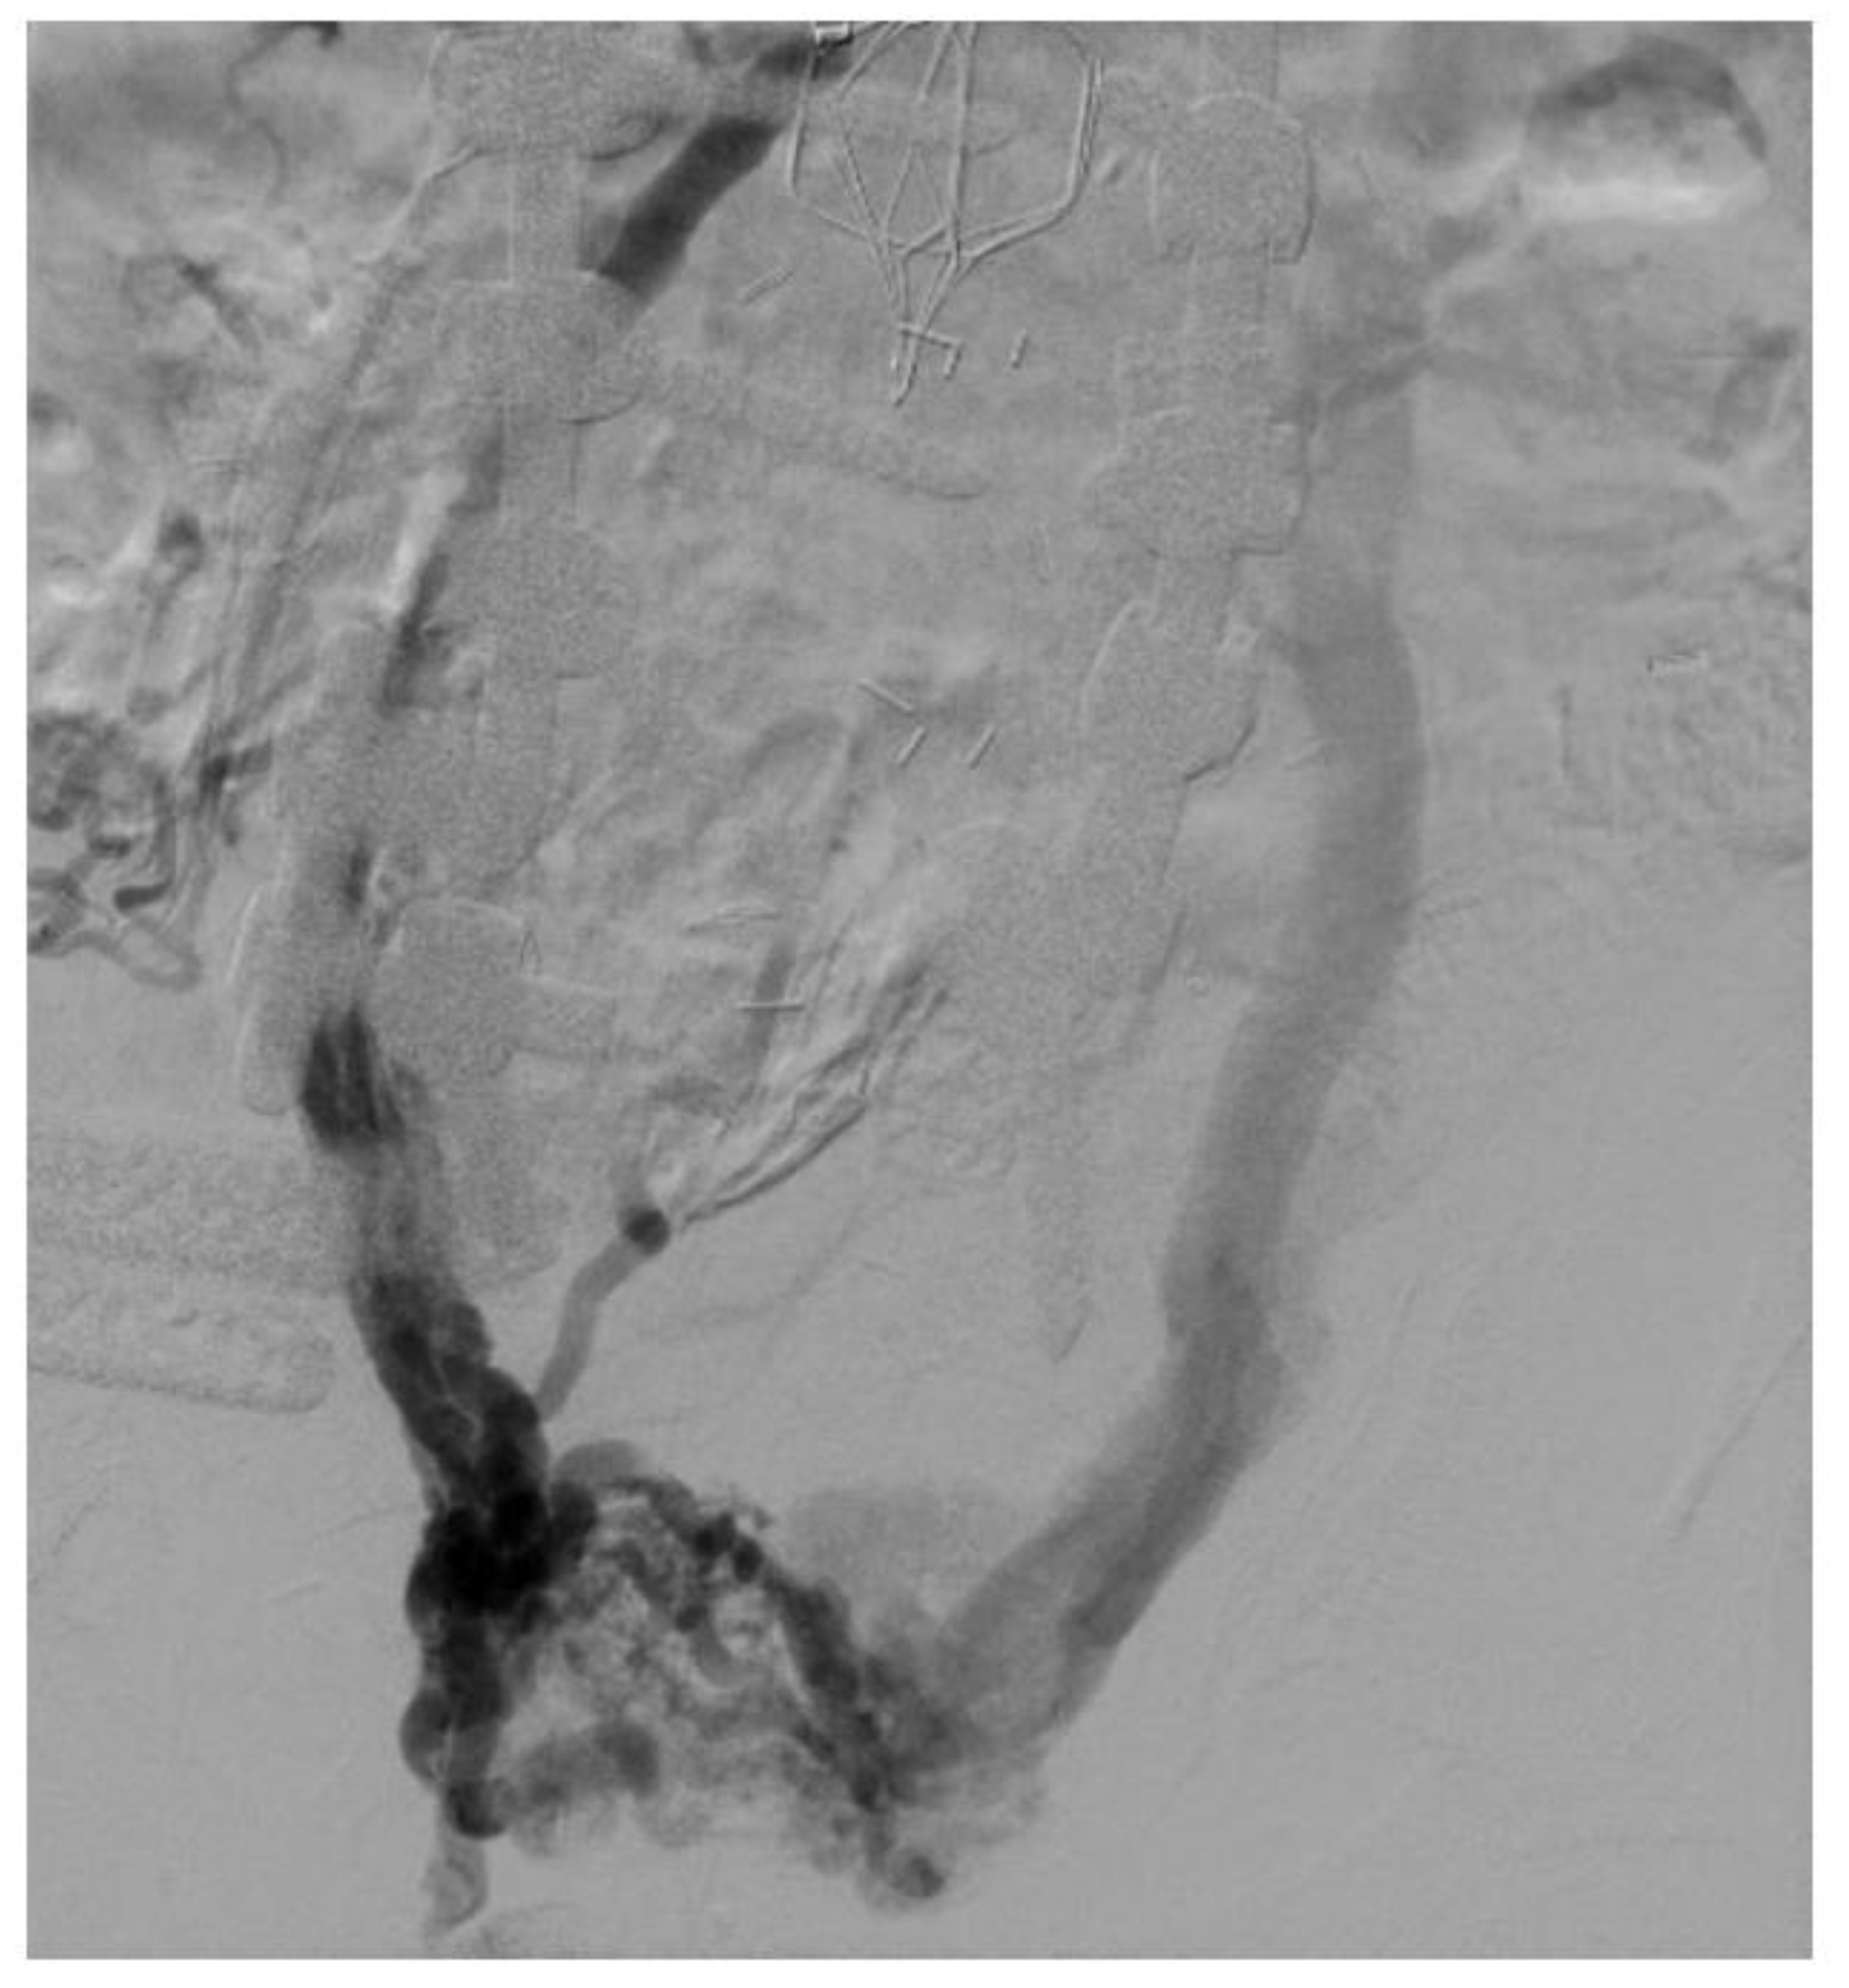

Figure 3.

Venogram showing in-stent restenosis in the stent (about 50%). Notice that the contrast does not completely fill the stent lumen.

In-stent restenosis (ISR) causes stent malfunction that can be unavoidable in certain cases (Figure 3). There are two important considerations with respect to ISR in patients with venous stents. Firstly, about 20–40% ISR is common in most venous stents. Secondly, ISR very rarely leads to complete stent occlusion (<10%). This in turn has led to two modifications in stenting techniques: firstly, slightly oversizing of Wallstents is recommended so that it can somewhat compensate for future development of ISR while also allowing for more aggressive balloon dilatation. Secondly, there is no role or recommendation for the prophylactic balloon dilatation of stents with ISR in asymptomatic individuals. ISR is affected by two main factors: a stent inflow area <125 mm2 and shear rate >100 s−1. Tapered stent profile may help with the latter. Drug eluting balloons and stents also represent a future area of research in the prevention of ISR in the iliofemoral venous system but the large surface area involved compared to arterial or coronary systems must be carefully considered [32,33].